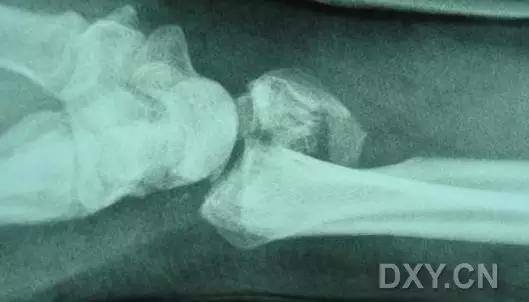

5. Hoffa 骨折

指股骨远端冠状面的骨折。

病例 1:一般股骨髁间、髁上粉碎骨折中含 Hoffa 骨折的不少见,但单纯后髁骨折则很少见。

第 2 例

第 3 例